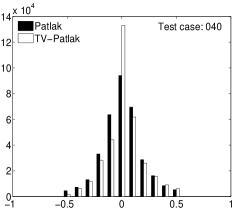

In the images shown in the figures we illustrate the calculated uptake rates of the FDG. Images for the CMRGlc can be obtained by directly scaling . In figure 1 we compare the result of using Patlak and TV-Patlak for estimating the uptake rates with respect to no noise, noise in the input function, Poisson noise in the sinogram, and finally with respect to the case in which the irreversibility assumption is violated but without noise in the sinogram or input data. In each case the histogram of the relative errors is given on the left, the Patlak image in the middle and the TV-Patlak on the right. The different scales in the histograms are due to the total number of results illustrated. When there is no noise (triples and ) the histogram illustrates results over all voxels but only one simulation, while for the noisy simulations the results are for all voxels over all realizations of the noise. The TV-Patlak images are more homogeneous in all cases and the relative errors are smaller. The figures clearly show the improvements of employing the TV-Patlak method as compared to using Patlak independently for each voxel. This is confirmed in figure 2 in which images with noise in the sinogram, positive and different noise levels in the input function are shown.